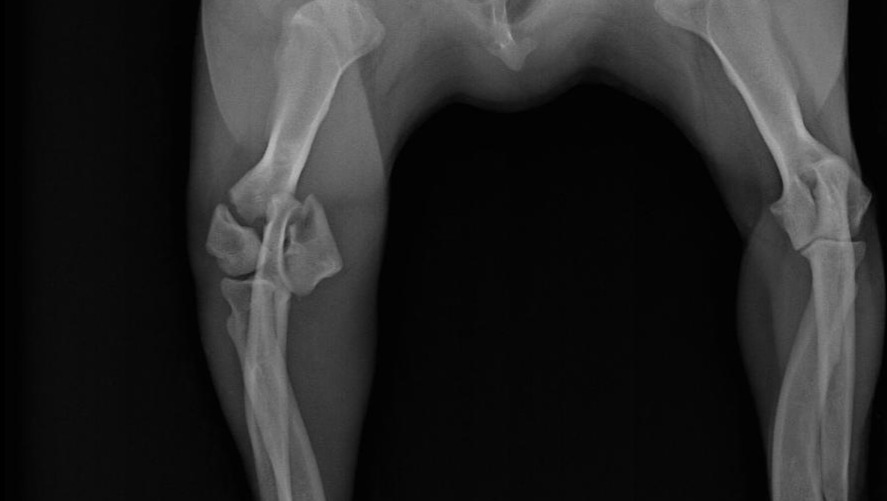

Hoy fui a ver a Friky a la Veterinaria Patas Descalzas. Despertó de la anestesia y está muy bien. En las nuevas radiografías ya se aprecio mejor y a detalle sus fracturas, que fueron en 3 partes. Entonces ya autoricé para que se le realice la cirugía indicada, que se realizará el Jueves 25 y se quedará todavía hasta el Lunes 29 para estar en observación y recuperación. El total de todo el proceso se me costeo al final a 7000 MXN, hoy pague la mitad y con sus donaciones terminaré de pagar lo que falta y para comprar medicamentos que se me indiquen para su tratamiento que falte. Nuevamente les agradezco a todos los que me apoyaron, yo sé quiénes son, así que estoy eternamente agradecido, no solamente yo, también Friky. Aún así los mantendré al tanto de lo que suceda en próximos días. Saludos!